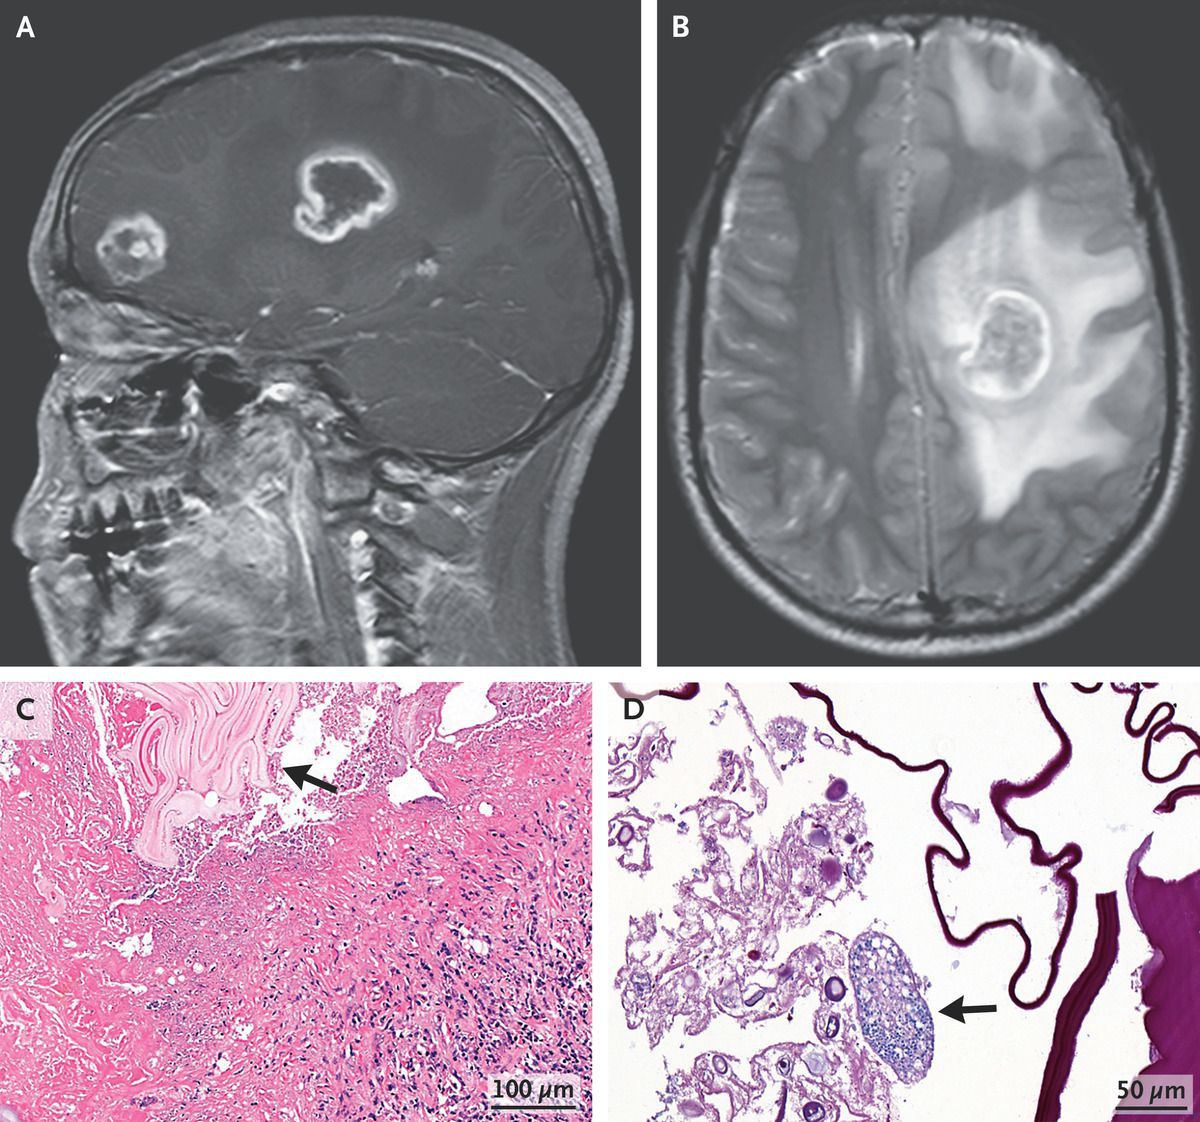

A 17-year-old boy presented to the emergency department with a 3-week history of dizziness, headache, and weakness of the right leg. Neurologic examination was notable for 4/5 strength in the right lower leg. Computed tomography (CT) of the head revealed ring-enhancing lesions in the frontal lobe and basal ganglia on the left side. Subsequent magnetic resonance imaging of the head also showed the lesions (Panel A; sagittal view, T1-weighted) as well as surrounding edema and midline shift (Panel B; axial view, T2-weighted). Testing for Echinococcus multilocularis and E. granulosus IgG antibodies was negative. Surgical excision of the lesions was performed. Histopathological testing showed necrotic tissue with surrounding granulomatous inflammation and an echinococcal laminated membrane (Panel C, arrow) as well an intact cyst (Panel D, arrow). A reverse-transcriptase–polymerase-chain-reaction assay identified E. multilocularis. CT imaging of the chest and abdomen did not show any other sites of disease. A diagnosis of primary cerebral alveolar echinococcosis was made. Alveolar echinococcosis is an invasive type of echinococcal infection that leads to tissue inflammation and destruction. The causative tapeworm is acquired by means of close contact with infected animals, which this patient had not reported. Postoperatively, a long course of albendazole was prescribed. At 2 months of follow-up, the patient’s symptoms had resolved.